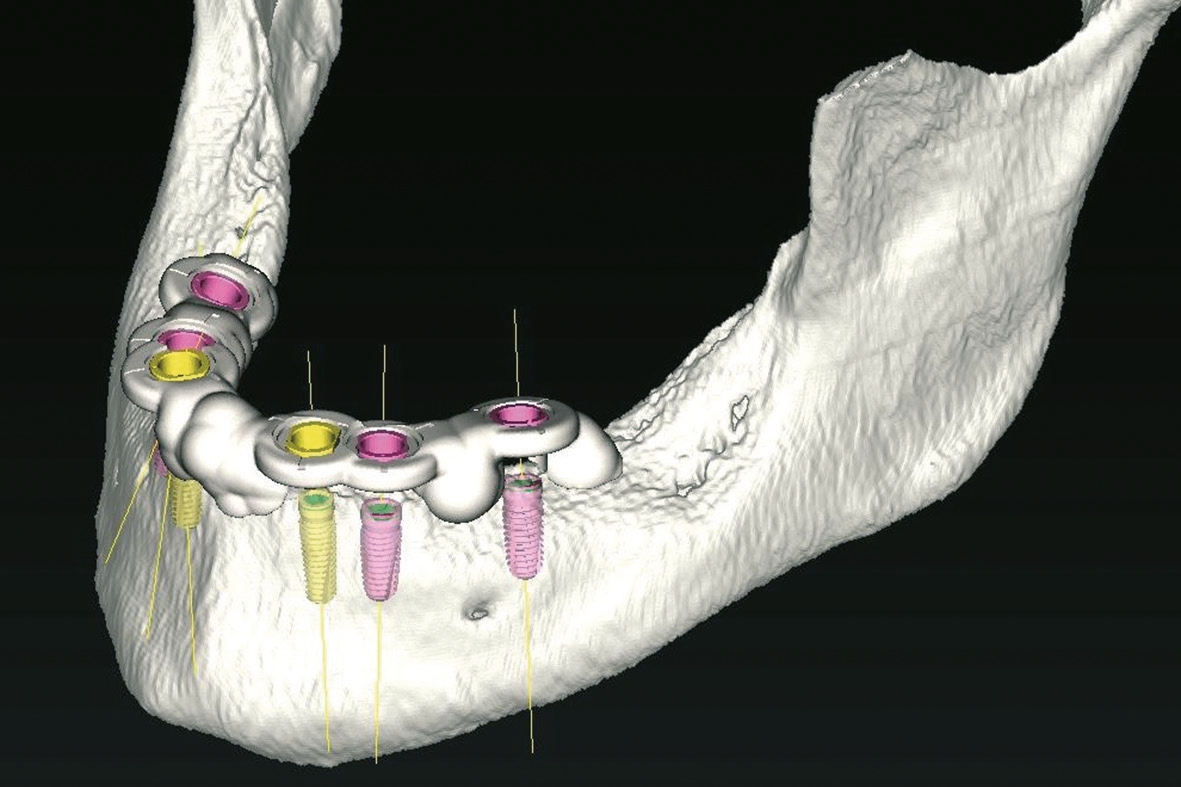

- Virtuelle Planung der möglichen Implantatpositionen und Evaluation, ob eine festsitzende Versorgung ohne Beckenkammaugmentation durchführbar ist. Die Analyse ergab, dass eine Versorgung im Oberkiefer mit acht Implantaten und im Unterkiefer mit sechs Implantaten für ein festsitzendes Zahnersatz-Konzept zwar implantologisch anspruchsvoll, aber durchführbar wäre. Daraufhin wurden die optimalen Implantatpositionen sowohl in Bezug auf den verfügbaren Knochen als auch das prothetische Ziel definiert und in der Planungssoftware (coDiagnostiX) festgelegt (Abb. 3-5).

Zur Übertragung der virtuellen Implantatposition in den OP Situs wurden knochengetragene Bohrschablonen virtuell konstruiert (Abb. 6-7).

Die Schablonen wurden in einem 3D-Druckverfahren hergestellt und mit Bohrhülsen für das Camlog Guide System versehen (Abb. 8-9). Hierbei handelt es sich um ein speziell abgestimmtes Bohrersystem zur sog. „full guided“ Implantation, d. h. nicht nur alle Bohrschritte von der Pilotbohrung bis zur fi nalen Aufbereitung und ggf. Gewindeschnitt, sondern auch die Implantatinsertion wird durch die Schablone durchgeführt. Intraoperativ wurde zunächst ein Mukoperiostlappen zur Darstellung des krestalen Knochens präpariert, was eine sichere und reproduzierbare Positionierung der Schablonen auf den Knochenauflagen ermöglichte. Danach erfolgte die full guided Insertion von Camlog Implantaten mit dem Camlog Guide Abb. 7: Planung der UK-Bohrschablone (Labor Cera-Technik, München). Abb. 8: OK-Bohrschablone mit eingearbeiteten Bohrhülsen (Labor Cera-Technik, München). Abb. 9: OK-Bohrschablone von basal mit den Knochenauflagen (Labor Cera- Technik, München). Abb. 10: Full guided Insertion der Implantate durch die Schablone. Bohrersatz in regio 16, 14, 13, 11, 21, 23, 24, 26 sowie 36, 34, 33, 43, 44, 46 (Abb. 10-12). Schon während der virtuellen Planung wurde dabei das Ausmaß ggf. zusätzlich notwendiger Augmentationen festgelegt und es erfolgte nach Abnahme der Schablonen an den geplanten Stellen autologe Augmentationen mit autologen Knochenblöcken (Abb. 13- 14).

Im vorgestellten Fall konnte eine festsitzende Versorgung trotz eines zum Teil extrem kompromittierten Knochenangebotes realisiert werden. Die Erfahrung zeigt hierbei, dass gerade komplexe Planungen am besten im Team aus Zahntechniker und Behandler gemeinsam erarbeitet werden. Besonderes Augenmerk wurde im vorliegenden Fall auf die knöcherne Abstützung der Schablonen gelegt, da im zahnlosen Kiefer eine sichere Lagefixierung der Bohrschablonen nur über Knochenauflagen oder über temporäre Hilfsimplantate erreicht werden kann. Diese sichere Fixierung stellt aber eine conditio sine qua non in der computernavigierten Implantologie dar und ist für die Genauigkeit der Übertragung der geplanten Implantatpositionen entscheidend [8]. Die Möglichkeit zur „flapless Surgery“, also die Implantate direkt transgingival zu setzen, besteht dabei nur bei zahngetragenen Bohrschablonen oder bei der Verwendung von Hilfsimplantaten. Da alle Navigationssysteme zwangsläufig eine technisch begrenzte Genauigkeit aufweisen, muss hierbei ein ausreichender Sicherheitsabstand zu anatomisch kritischen Strukturen bei der Implantatplanung mit berücksichtigt werden [9].